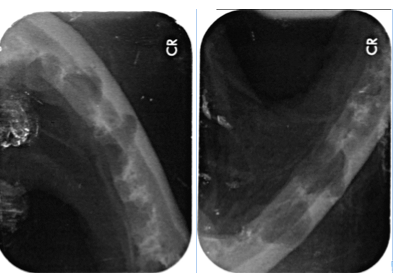

In Narkose sah man auf Leilas Röntgenbildern dann das gesamte Ausmaß ihrer Zahnerkrankung. Bis auf die Canini wiesen alle Zähne hochgradige Wurzelentzündungen mit Osteolysen des Kieferknochens auf. Deshalb konnte man auch schon von außen die Zahnhälse freiliegend sehen. Im Wurzelbereich waren die Veränderungen so schlimm, dass der Unterkiefer kurz vor einer Fraktur stand.

Natürlich versuchen wir immer so viele Zähne wie möglich zu erhalten. Eine Füllung der betroffenen Zähne, hätte die Entzündung nicht eindämmen können und eine zusätzliche Wurzelspitzenresektion wäre vonnöten gewesen. Da jedoch fast jeder einzelne Zahn betroffen war und der Kiefer sowieso schon sehr wenig Halt besaß, wurde auf eine zusätzliche Traumatisierung durch das Aufbohren des Kiefers verzichtet. Daher war der Erhalt der Zähne in diesem Fall nicht möglich. Hätten wir die Zähne drin gelassen, hätte sich der Kieferknochen nicht erholen können und wäre sicher demnächst gebrochen.

Es ist in so einer Situation auch durchaus möglich, dass der Kiefer intra OP frakturiert sobald der Zahn extrahiert wurde und dann kein Halt mehr besteht. Da jedoch der Zahn auch die Ursache der Entzündung ist, blieb keine andere Wahl, als alle Zähne mit der größtmöglichen Vorsicht zu extrahieren. Glücklicherweise blieb der Kiefer stabil und es musste keine Osteosynthese vorgenommen werden.